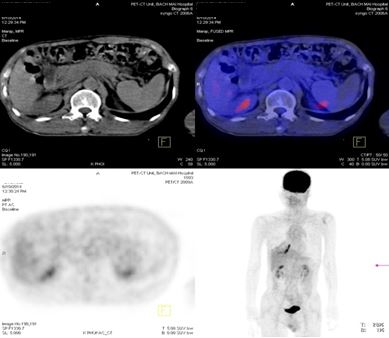

+ Nhiều hạch ổ bụng dọc theo ĐM chủ bụng tạo thành khối lớn KT 8,5x5,1 cm và 5,1x3,9cm, tăng hấp thu F-18 FDG, max SUV=10,45. Nhu mô gan hạ phân thùy VI có nốt KT 1,2cm, tăng hấp thu F-18 FDG, max SUV=4,15.

+ Chụp PET/ CT đánh giá lại sau 4 tháng điều trị.

-Trước điều trị: Nhiều hạch ổ bụng dọc theo ĐM chủ bụng tạo thành khối lớn KT 8,5x5,1 cm và 5,1x3,9cm,  max SUV=10,45.

-Sau điều trị 4 tháng: Không có hạch ổ bụng

Trước điều trị: Hạ phân thùy VI gan P có nốt 1,2cm, max SUV= 4,15. Hạch ổ bụng: 8,5x5,1 cm  max SUV=10,45

Sau điều trị 4 tháng: Không có tổn thương